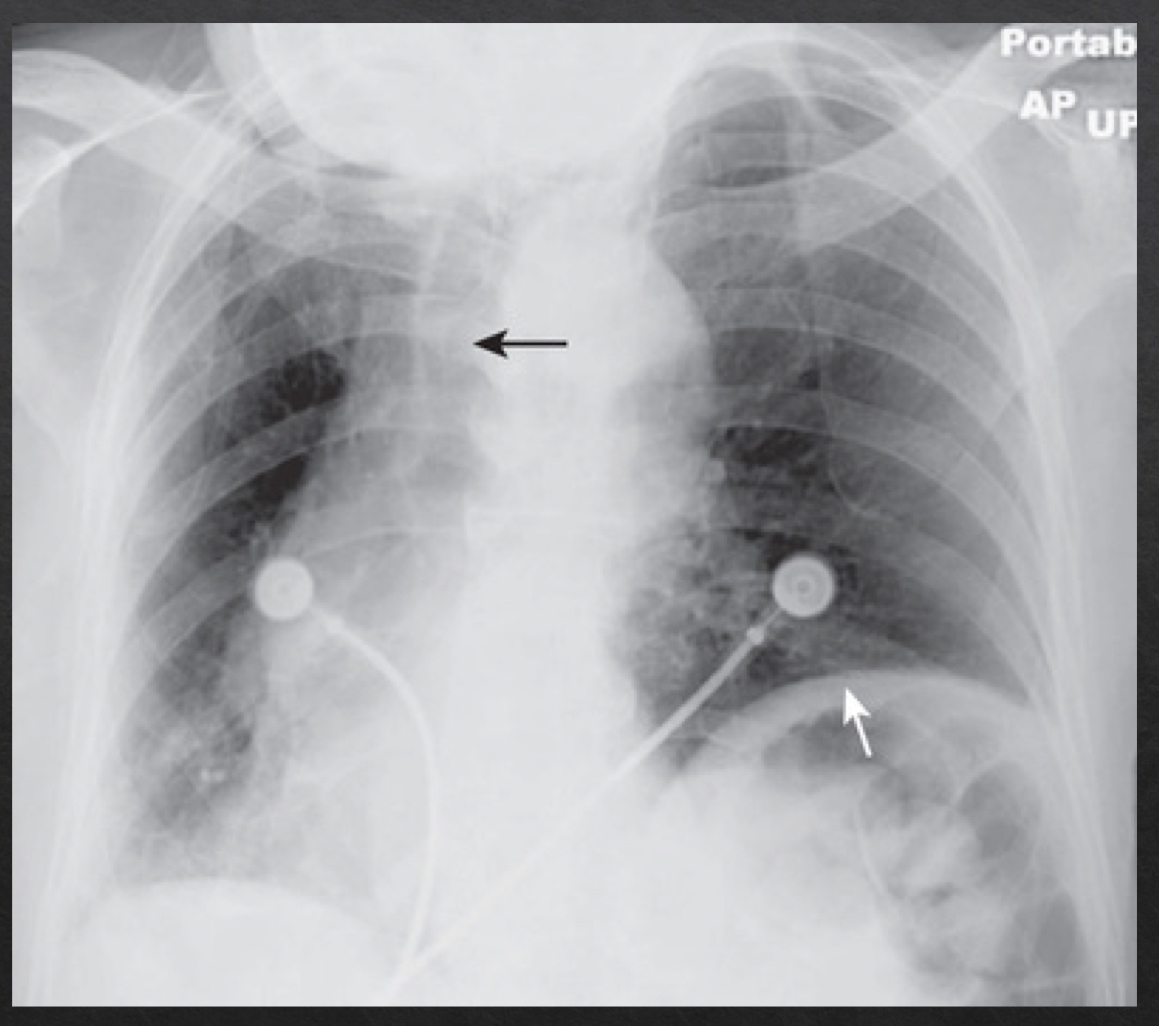

magnification

plays a role in assessing heart size

closer an object is to the surface on which it is being imaged, the more true to actual size the resultant object will be

PA view is more true to size

farther away → more magnified

AP view

angulation

orientation of xray beam passing through object

views:

horizontal- normal

parallel to floor

medial end of the clavicle superimposes on 3rd or 4th rib

over angulated

bedridden pts that cannto fully sit up

clavicles are projected above first rib